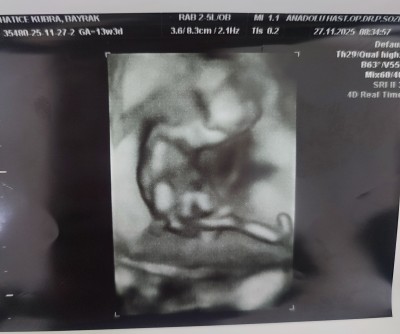

11 haftalık ve 13+5 haftalık ultrason görüntülerimiz doktor cinsiyette emin olamadi önce erkek sonra kız dedi ama sizin tahminleriniz neler?

Gebelik haftası 13+5

Bacak arasında uç cızgı var gıbı canm kıza benzettim bende